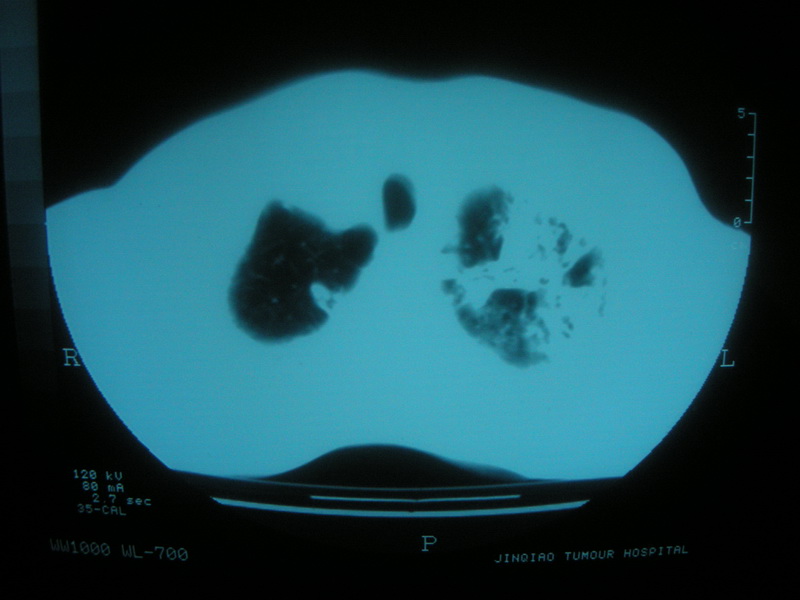

标题: CT11692:男,63岁,糖尿病史15年.抗炎治疗7天,病情 [打印本页]

标题: CT11692:男,63岁,糖尿病史15年.抗炎治疗7天,病情

请老师看看是结核还是炎症?

双肺继发性肺结核伴感染!

双肺继发性肺结核伴支气管播散。

考虑双肺继发性肺结核。